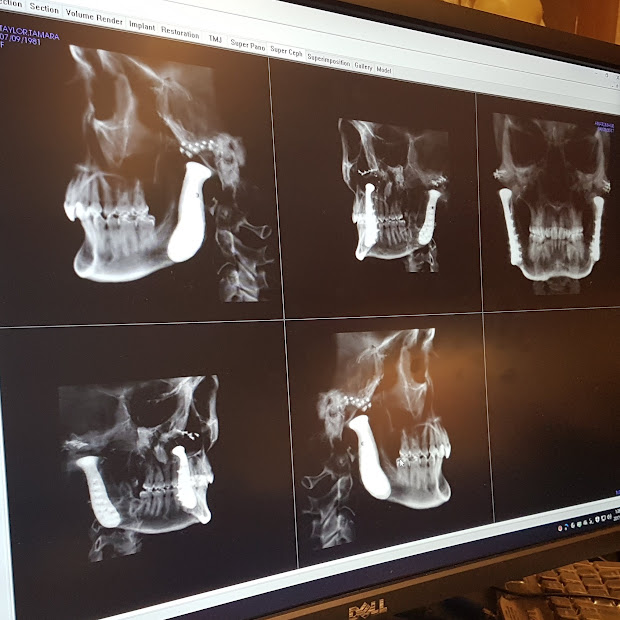

While I was busy living life, my TMJ continued to degrade. I was routinely driving to Edmonton (5 hours round trip) to the University of Alberta for injections to help me function and reduce the debilitating migraines that were plaguing me up to 4 times per week. I had gotten to the point where I couldn’t even drive myself anywhere without triggering a migraine so severe I would have to immediately pull over and check into a hotel. We finally came to the realization that the best opportunity for me to keep up with life and my busy young family was a total bilateral TMJ replacement.

I was scheduled for my surgery in February 2014. The diseased joints were removed but the completion of the surgery with placement of the prosthesis was aborted due to the discovery of contamination in the OR. I waited until April 2014 for my second surgery to place the new prosthesis joints in place. Recovery was slow but steady, but in August 2014 I ended up with an infection in my right prosthetic which required twice daily travel to the hospital for IV antibiotics for many weeks. My kids got reallllly good at being patient and ate their fair share of hospital popsicles during this period of life. As a result of spending so much time in a hospital setting I ended up with C. diff infection so began an entirely new batch of antibiotics to treat that. It was an incredibly difficult season of life.

The repeated surgeries resulted in complete loss of nerve sensation in most of my face, lips and tongue. Speaking and eating became difficult due to frequently biting myself. As the new TMJ prosthesis settled into place my bite changed significantly. My bottom jaw had receded to the point where my lower incisors rested on my upper palate. It was decided that I would undergo orthodontics (braces) followed by a lower jaw advancement via sagittal split osteotomy. I underwent this third jaw surgery in 2018.

In 2021 I underwent the initial surgery to remove the right prosthesis and antibiotic block was put in the empty space to give it time to completely wipe out any remaining infection. The hope was to have this gentamycin block in place for 3 months. Unfortunately, due to complications with COVID restrictions and surgeries I had to wait 9 months to finally receive my brand new clean prosthesis. The unfortunate side effect of waiting 9 months without a joint meant a lot of soft tissue compensation and asymmetry which I am still struggling to rectify today.